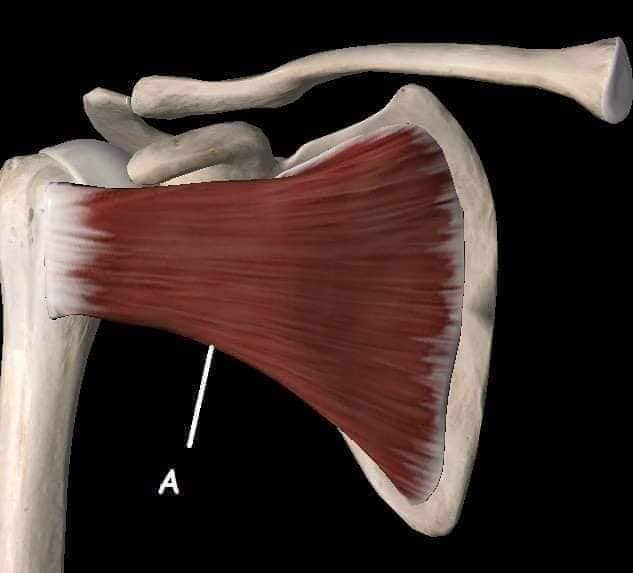

М'язи, що піднімають лопатку: Трапецієподібний м'яз: великий м'яз, що покриває верхню частину спини. Його функція - підтримка і рух лопаток, а також забезпечення стабільності хребта.